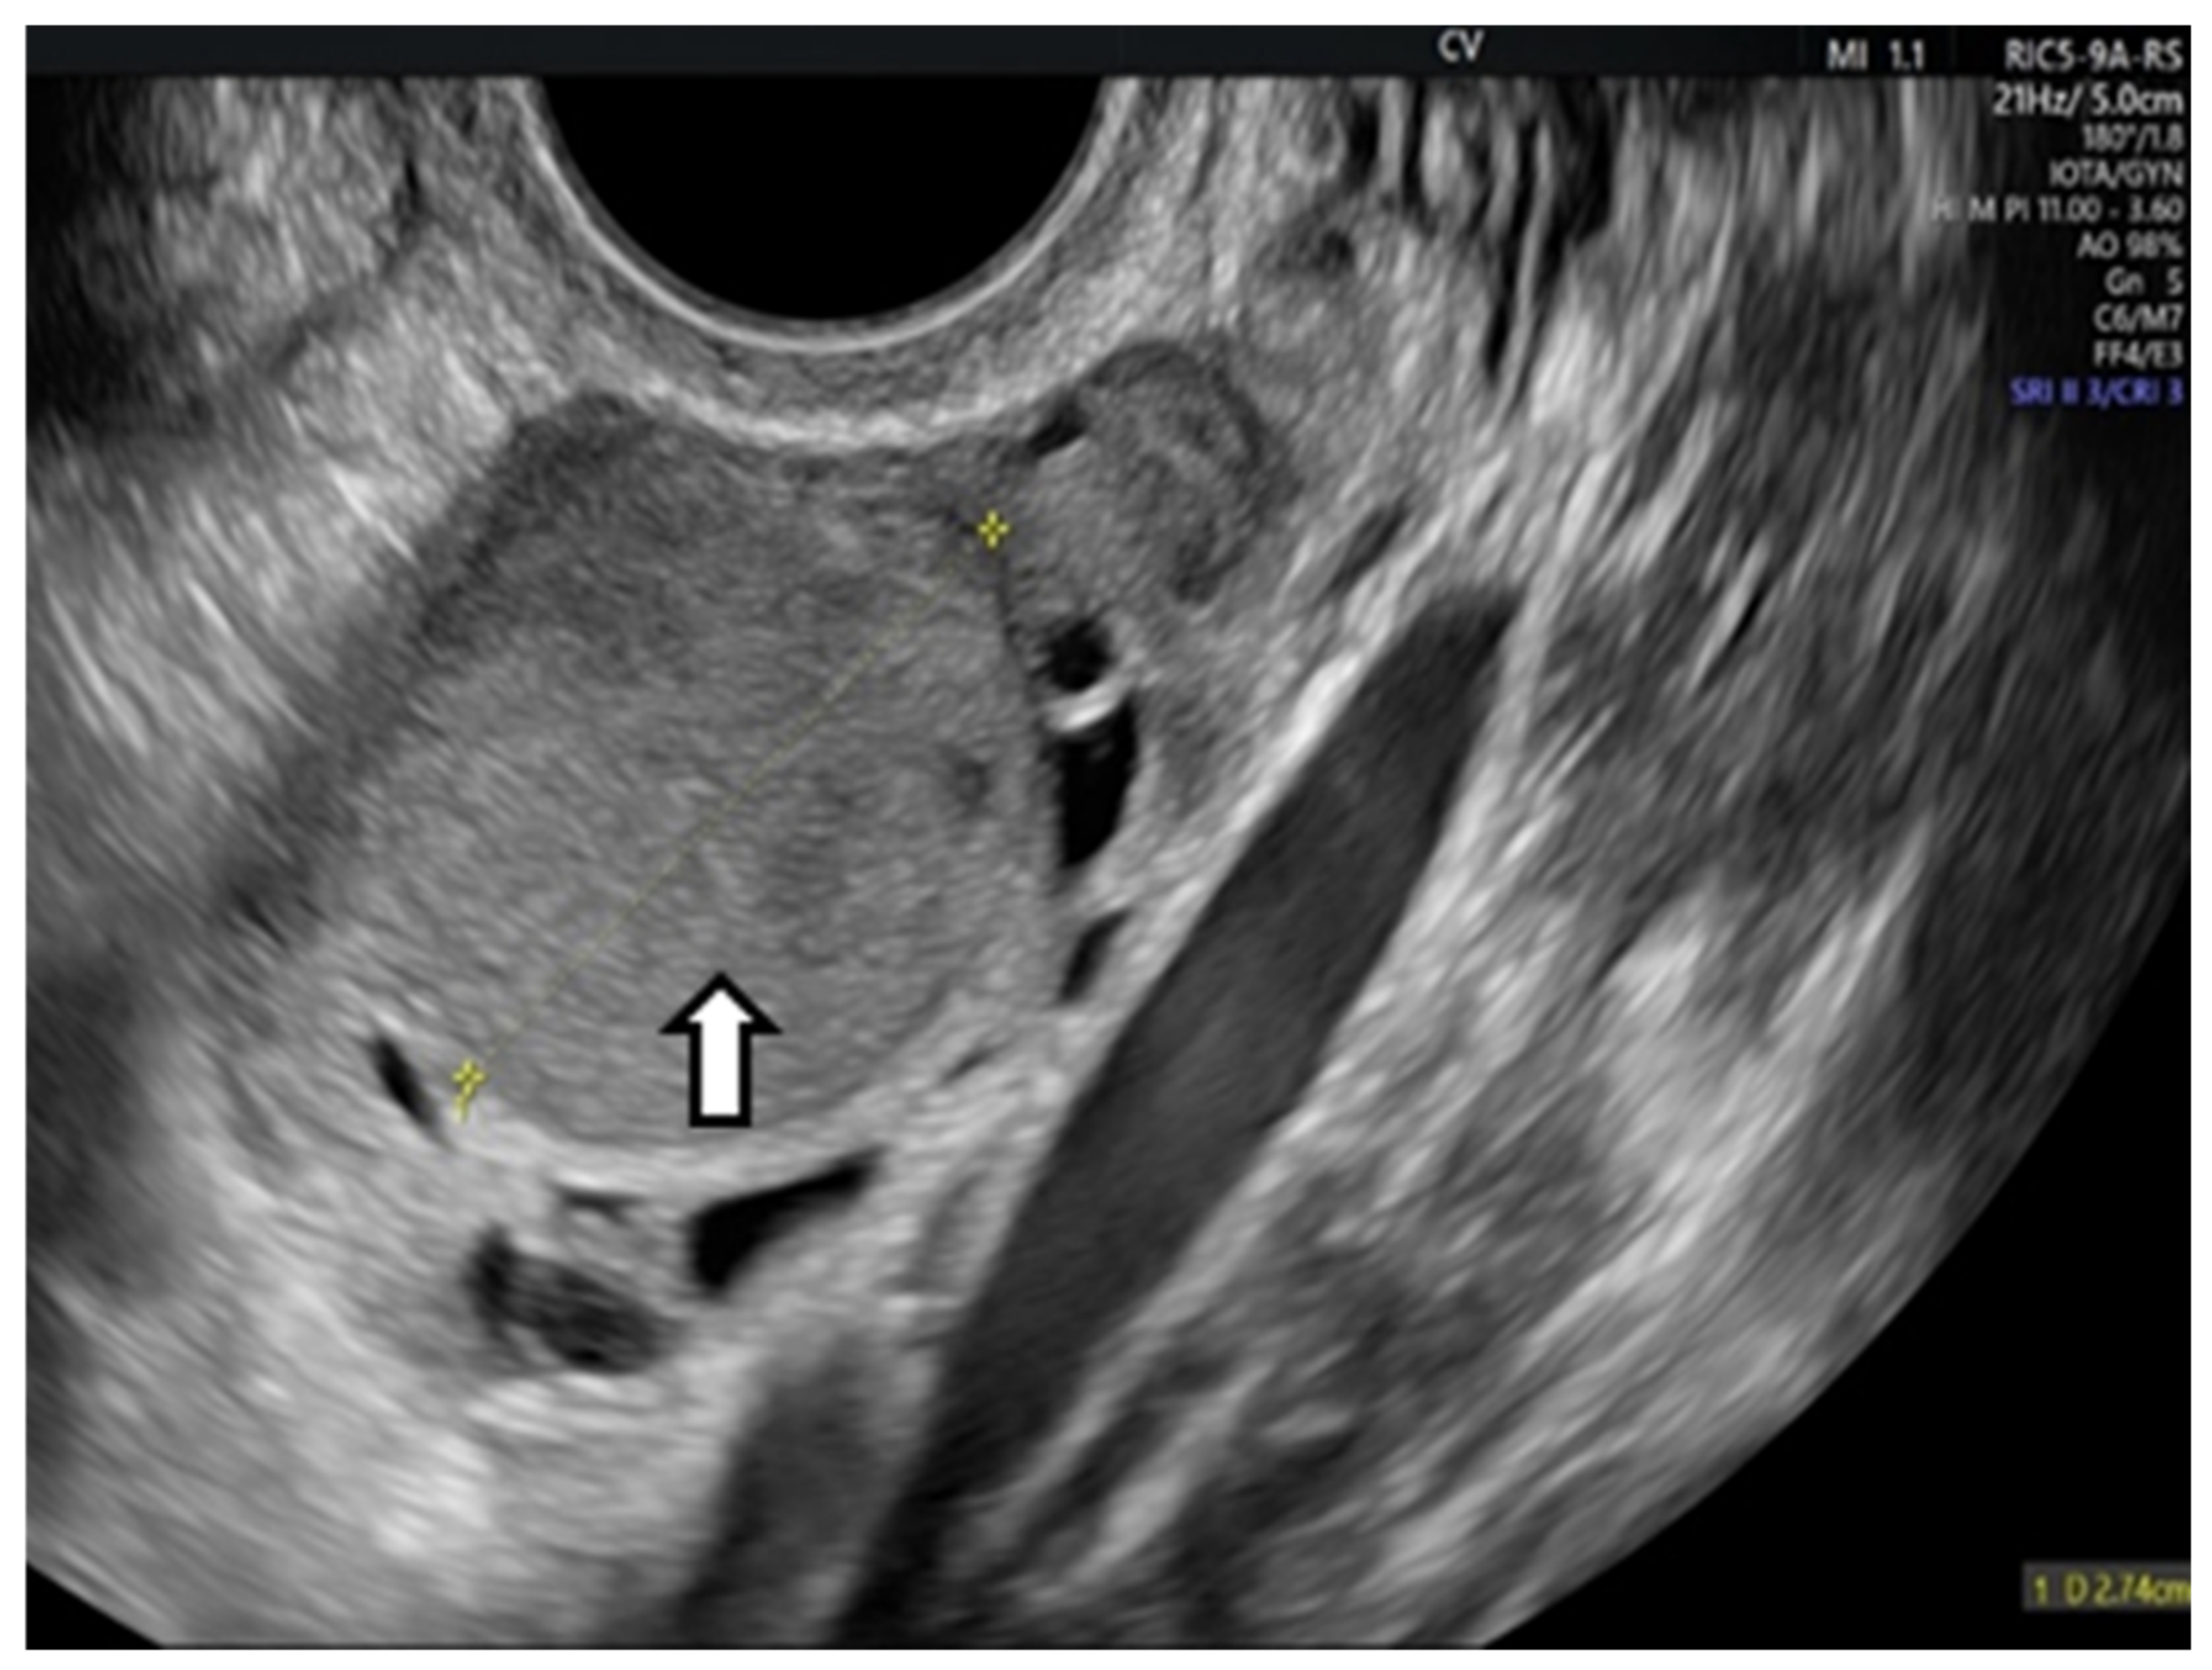

6.1.3. Imaging